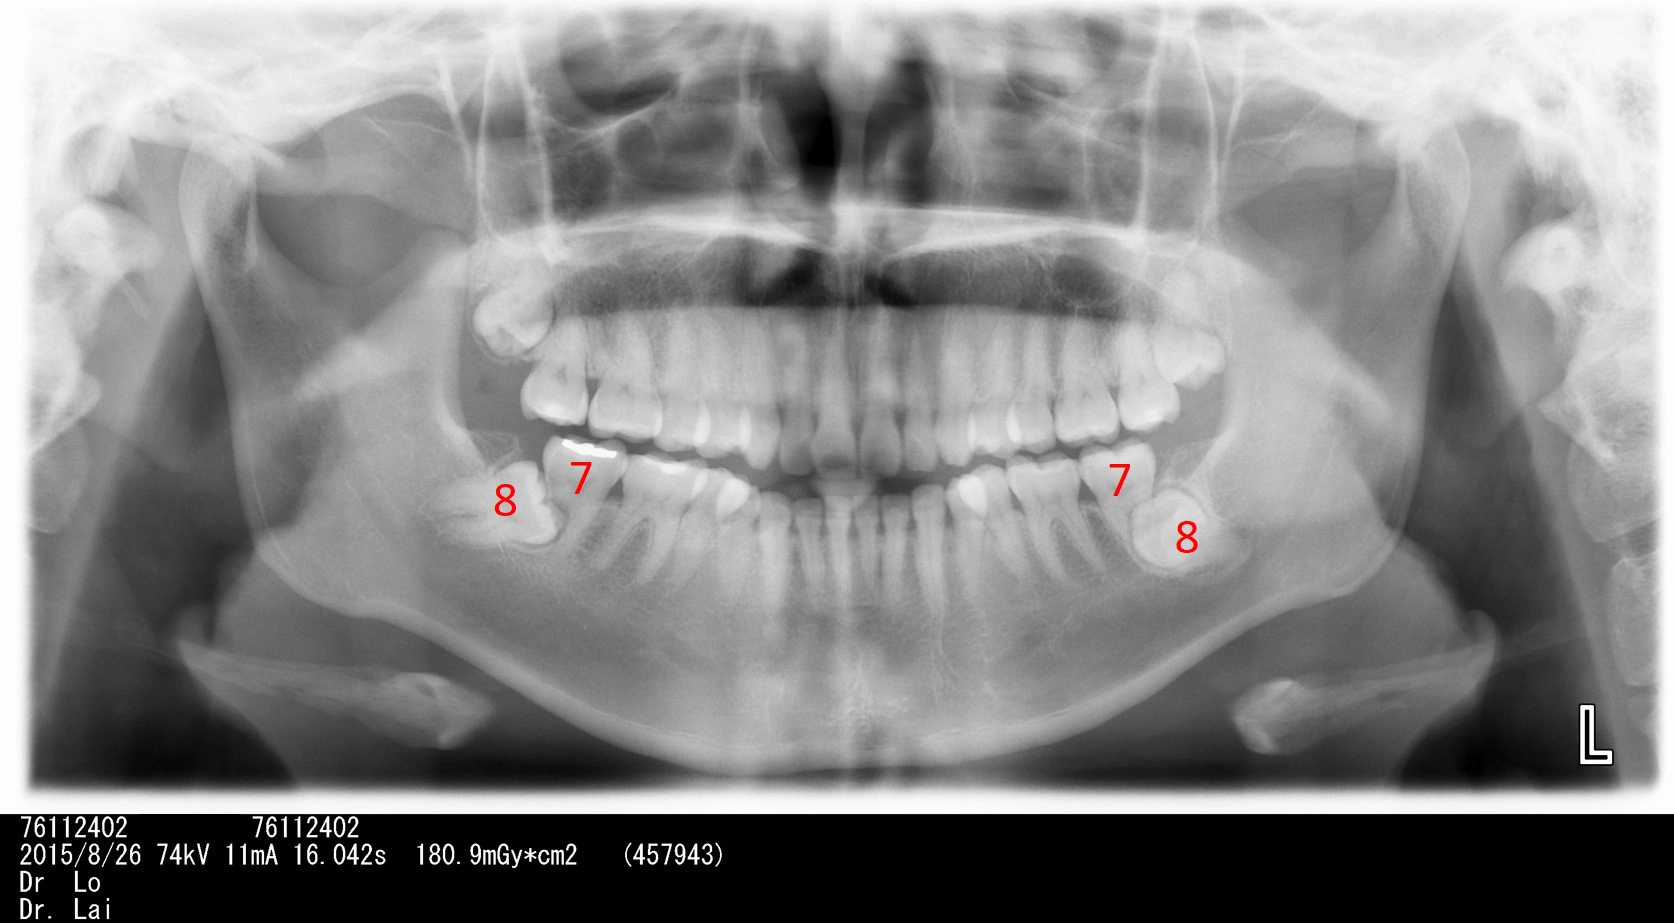

左右下牙兩顆智齒不聽醫師建議拔除,5年後,智齒前面大牙也因智齒而蛀牙,最後拔除4顆牙